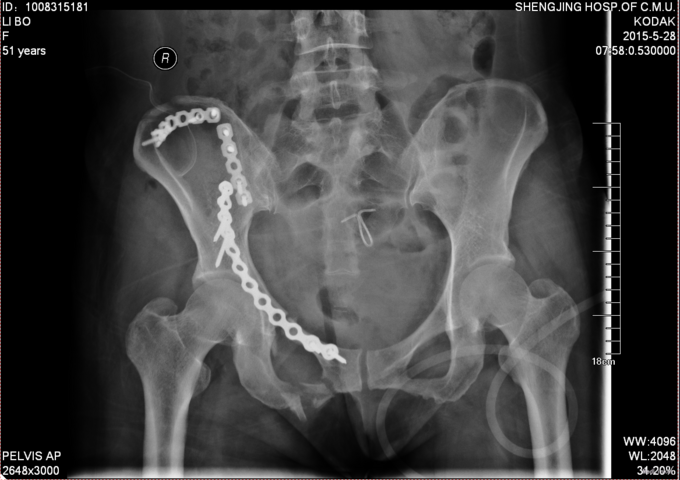

主诉:外伤后右髋部疼痛肿胀8天 现病史:患者于2015年5月16日发生车祸,伤后右髋部疼痛肿胀,下肢运动障碍,急诊120送至丹东市二医院,行骨盆平片,骨盆CT提示骨盆骨折,给予输血补液、骨牵引及留置尿管等对症治疗,急诊以“骨盆骨折”为主要诊断收入我科,患者病来无头晕头痛,无恶心呕吐,留置导尿中,大便正常。

专科查体:患者平车入病房,右侧髋部瘀斑,压痛(+),叩击痛(+),骨盆分离挤压试验(+),双下肢感觉未见异常,足趾活动可,双侧足背动脉搏动可触及。

诊断:骨盆骨折(Tile B1) 患者入院后完善检查后,全麻下行骨盆骨折切开复位钢板内固定术,术后给予抗炎,消肿,冷敷,患肢抬高等对症治疗。患者每天换药观察切口愈合情况,无红肿及渗出,待伤口14天后予以拆线治疗,予以出院,给予康复处方。